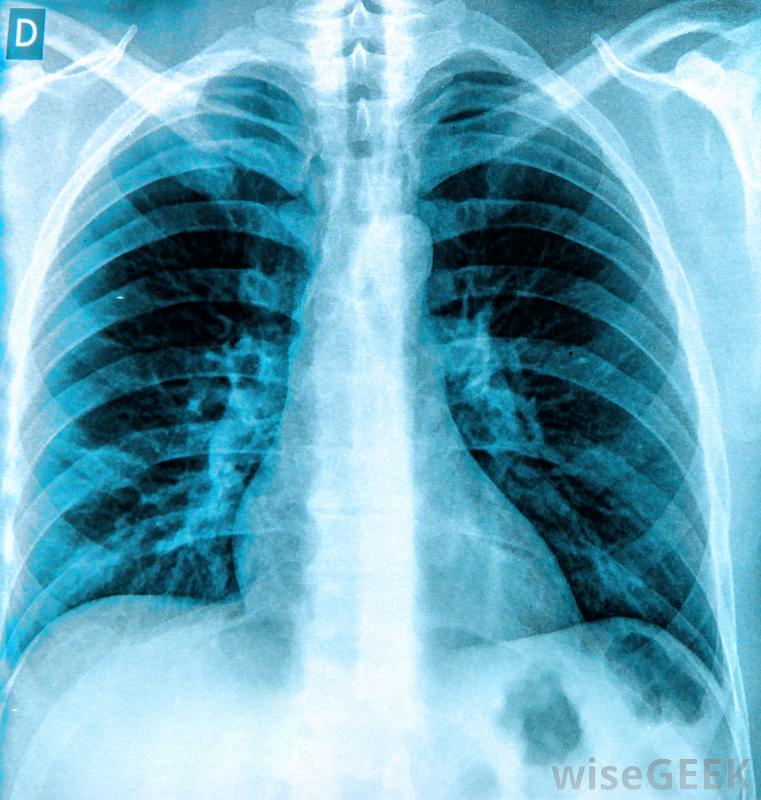

可以通过X光片来诊断胸腔积液在健康的肺中,胸膜膜层之间很少有液体。过剩的液体通常是由创伤或某种疾病引起的,如癌症、感染或心力衰竭。在这种情况下,胸膜穿刺是一种诊断方法,抽取液体样本并检测是否存在细菌,病毒或其他提示液体积聚原因的线索。

胸膜穿刺后可立即进行胸部X光检查以确保肺部没有受损。